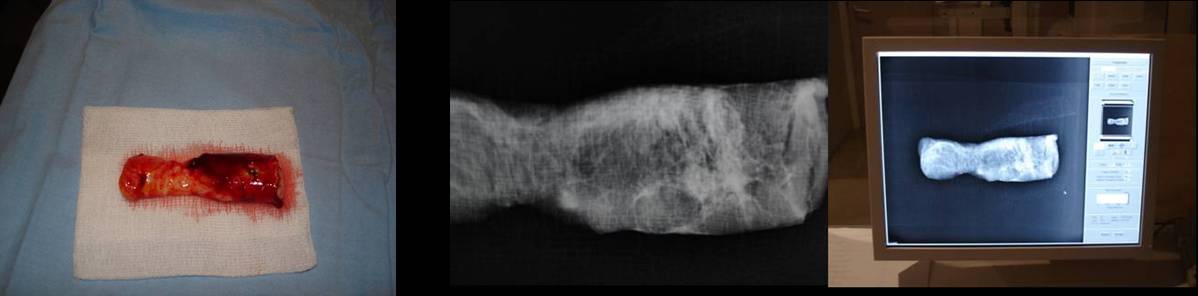

- Realitzem dues projeccions radiològiques crani - caudal i lateral 90 º. L’objectiu és comprovar que tant la lesió com els marges estan inclosos a la peça extreta.

- Es col·loquen la mostra extreta a un recipient amb formol al 10%.